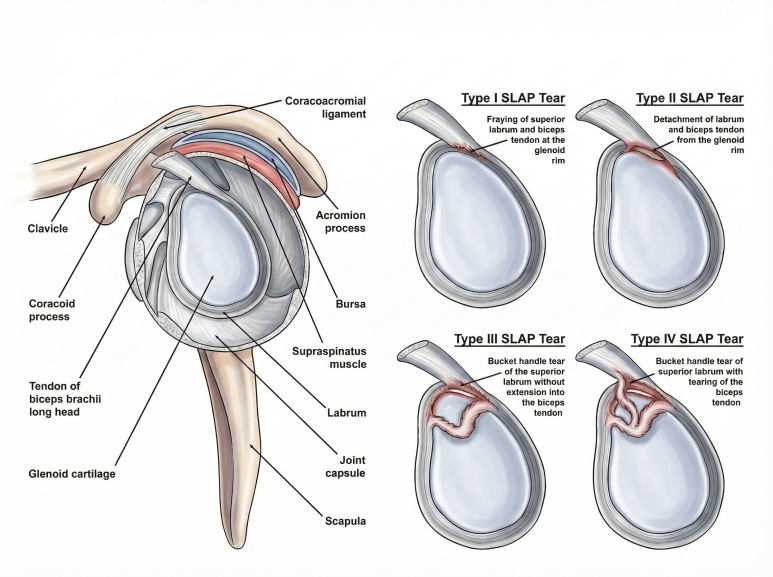

어깨 관절의 기능을 회복시켜서즉각적으로 통증을 해결한 최신 치료 사례입니다.** 특히 이 치료는 ‘눈으로 보면서’ 염증 유착 부위를 시술하는 바로 의 가치를 보여줍니다. > SLAP 병변, > > 단순한 구조적 문제가 아닙니다. SLAP 병변 (Superior Labral Anterior Posterior Lesion)은 주로 야구 투수나 기계체조 선수처럼**

어깨를 많이 쓰는 운동선수들에게

발생하는 흔한 과사용 손상입니다.

어깨뼈에 팔뼈를 고정하는

관절와순(Labrum)이 찢어지는 것인데요.

주로팔을 머리 위로 올릴 때*

통증이 나타나는 것이 특징입니다. 기존에는 약물, 주사, 재활 치료를 먼저 진행했고

오래 지속된 왼쪽 어깨 통증이 있었고,** 특히나 링 위에서 ‘자이언트 스윙’을 할 때 심한 통증을 느꼈는데요.  MRI 촬영 결과 Type 2 SLAP 병변이 확인되었지만 재활에도 통증이 개선되지 않아 다른 관점으로 접근이 필요했습니다. SLAP 병변은 무증상인 경우도 많아서 지금 당장 아픈 원인이 아닌 경우가 있는데요. 다른 부분들 먼저 치료하고도 해결이 안 될 때 수술을 고려합니다.

MRI 촬영 결과 Type 2 SLAP 병변이 확인되었지만 재활에도 통증이 개선되지 않아 다른 관점으로 접근이 필요했습니다. SLAP 병변은 무증상인 경우도 많아서 지금 당장 아픈 원인이 아닌 경우가 있는데요. 다른 부분들 먼저 치료하고도 해결이 안 될 때 수술을 고려합니다.  DOI: 10.7759/cureus.60157 여기서 주목한 점은 해당 선수가 SLAP 병변 외에도 어깨 관절의 '가동 범위 제한'이 심했다는 겁니다. 우리가 어깨 관절을 검사할 때 쓰는 두 가지 테스트에서 양성으로 나왔는데요. 1. 결합 외전 검사(CAT, Combined Abduction Test): 견갑골을 고정한 뒤 팔을 위로 올려(Flexion) 가동 범위가 줄어드는지 보는 검사 2. 수평 굴곡 검사(HFT, Horizontal Flexion Test): 어깨를 몸통 쪽으로 수평하게 모을 때 가동 범위가 줄어드는지 보는 검사